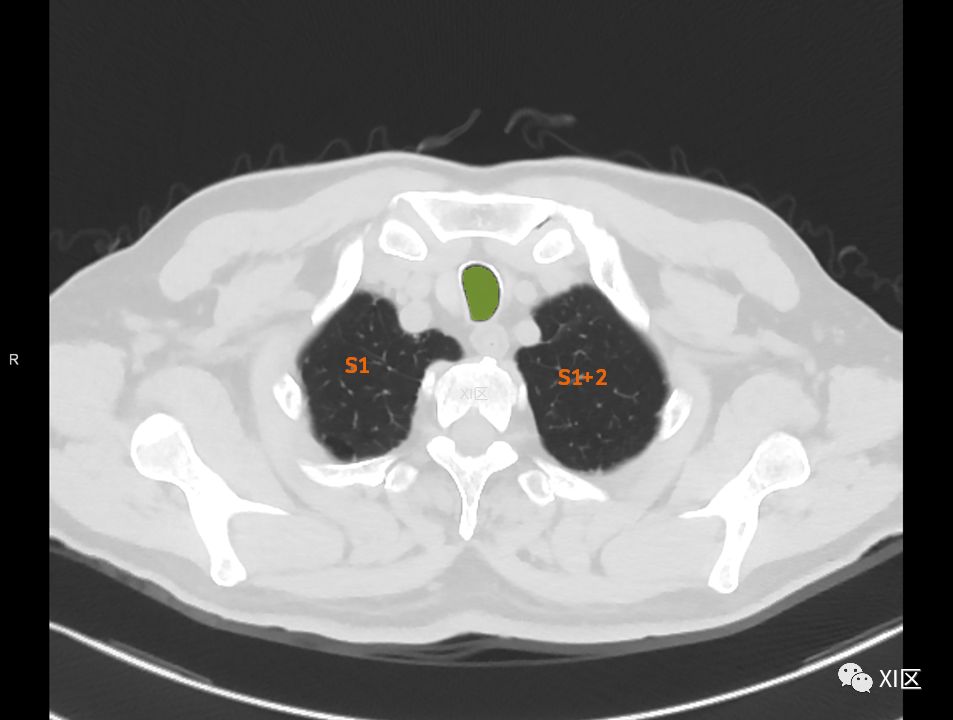

肺的分段

肺的断层分段示意图

在进行肺的分段时,可以上下观察浏览,沿着相应气管的走形可以更容易准确地进行分段。